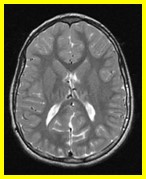

* 2. Which patient has the higher ICP?